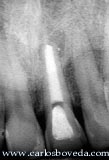

Recordemos que a la semana de haber ejecutado un retratamiento de conducto en 1 sesión en el incisivo central superior izquierdo (totalmente asintomático por años) el paciente regresa a consulta con una molestia importante en el periapice del diente. Aquí se puede apreciar la condición clínica y radiográfica del caso en este momento.

Clínicamente se aprecia una tumefacción en el fondo del vestibulo en relación a este diente. Radiográficamente no se aprecia mayor diferencia a lo visto en el momento de ejecutar el procedimiento.

Condición clínica y radiográfica del caso 1 mes después de haber ejecutado el procedimiento (tres semanas posterior a la agudización)

Secuencia radiográfica (diferentes angulaciones) que permiten apreciar la condición del caso 1 año después.

Comparación de la condición inicial y la lograda al año de ejecutar el retratamiento de conductos, al combinar la acción endodóntica y restauradora. La percepción clínica ya es aceptable para el paciente y no desea someterse a procedimientos más invasivos que perfeccionen la apariencia de este diente. Radiográficamente, el resultado es claro.